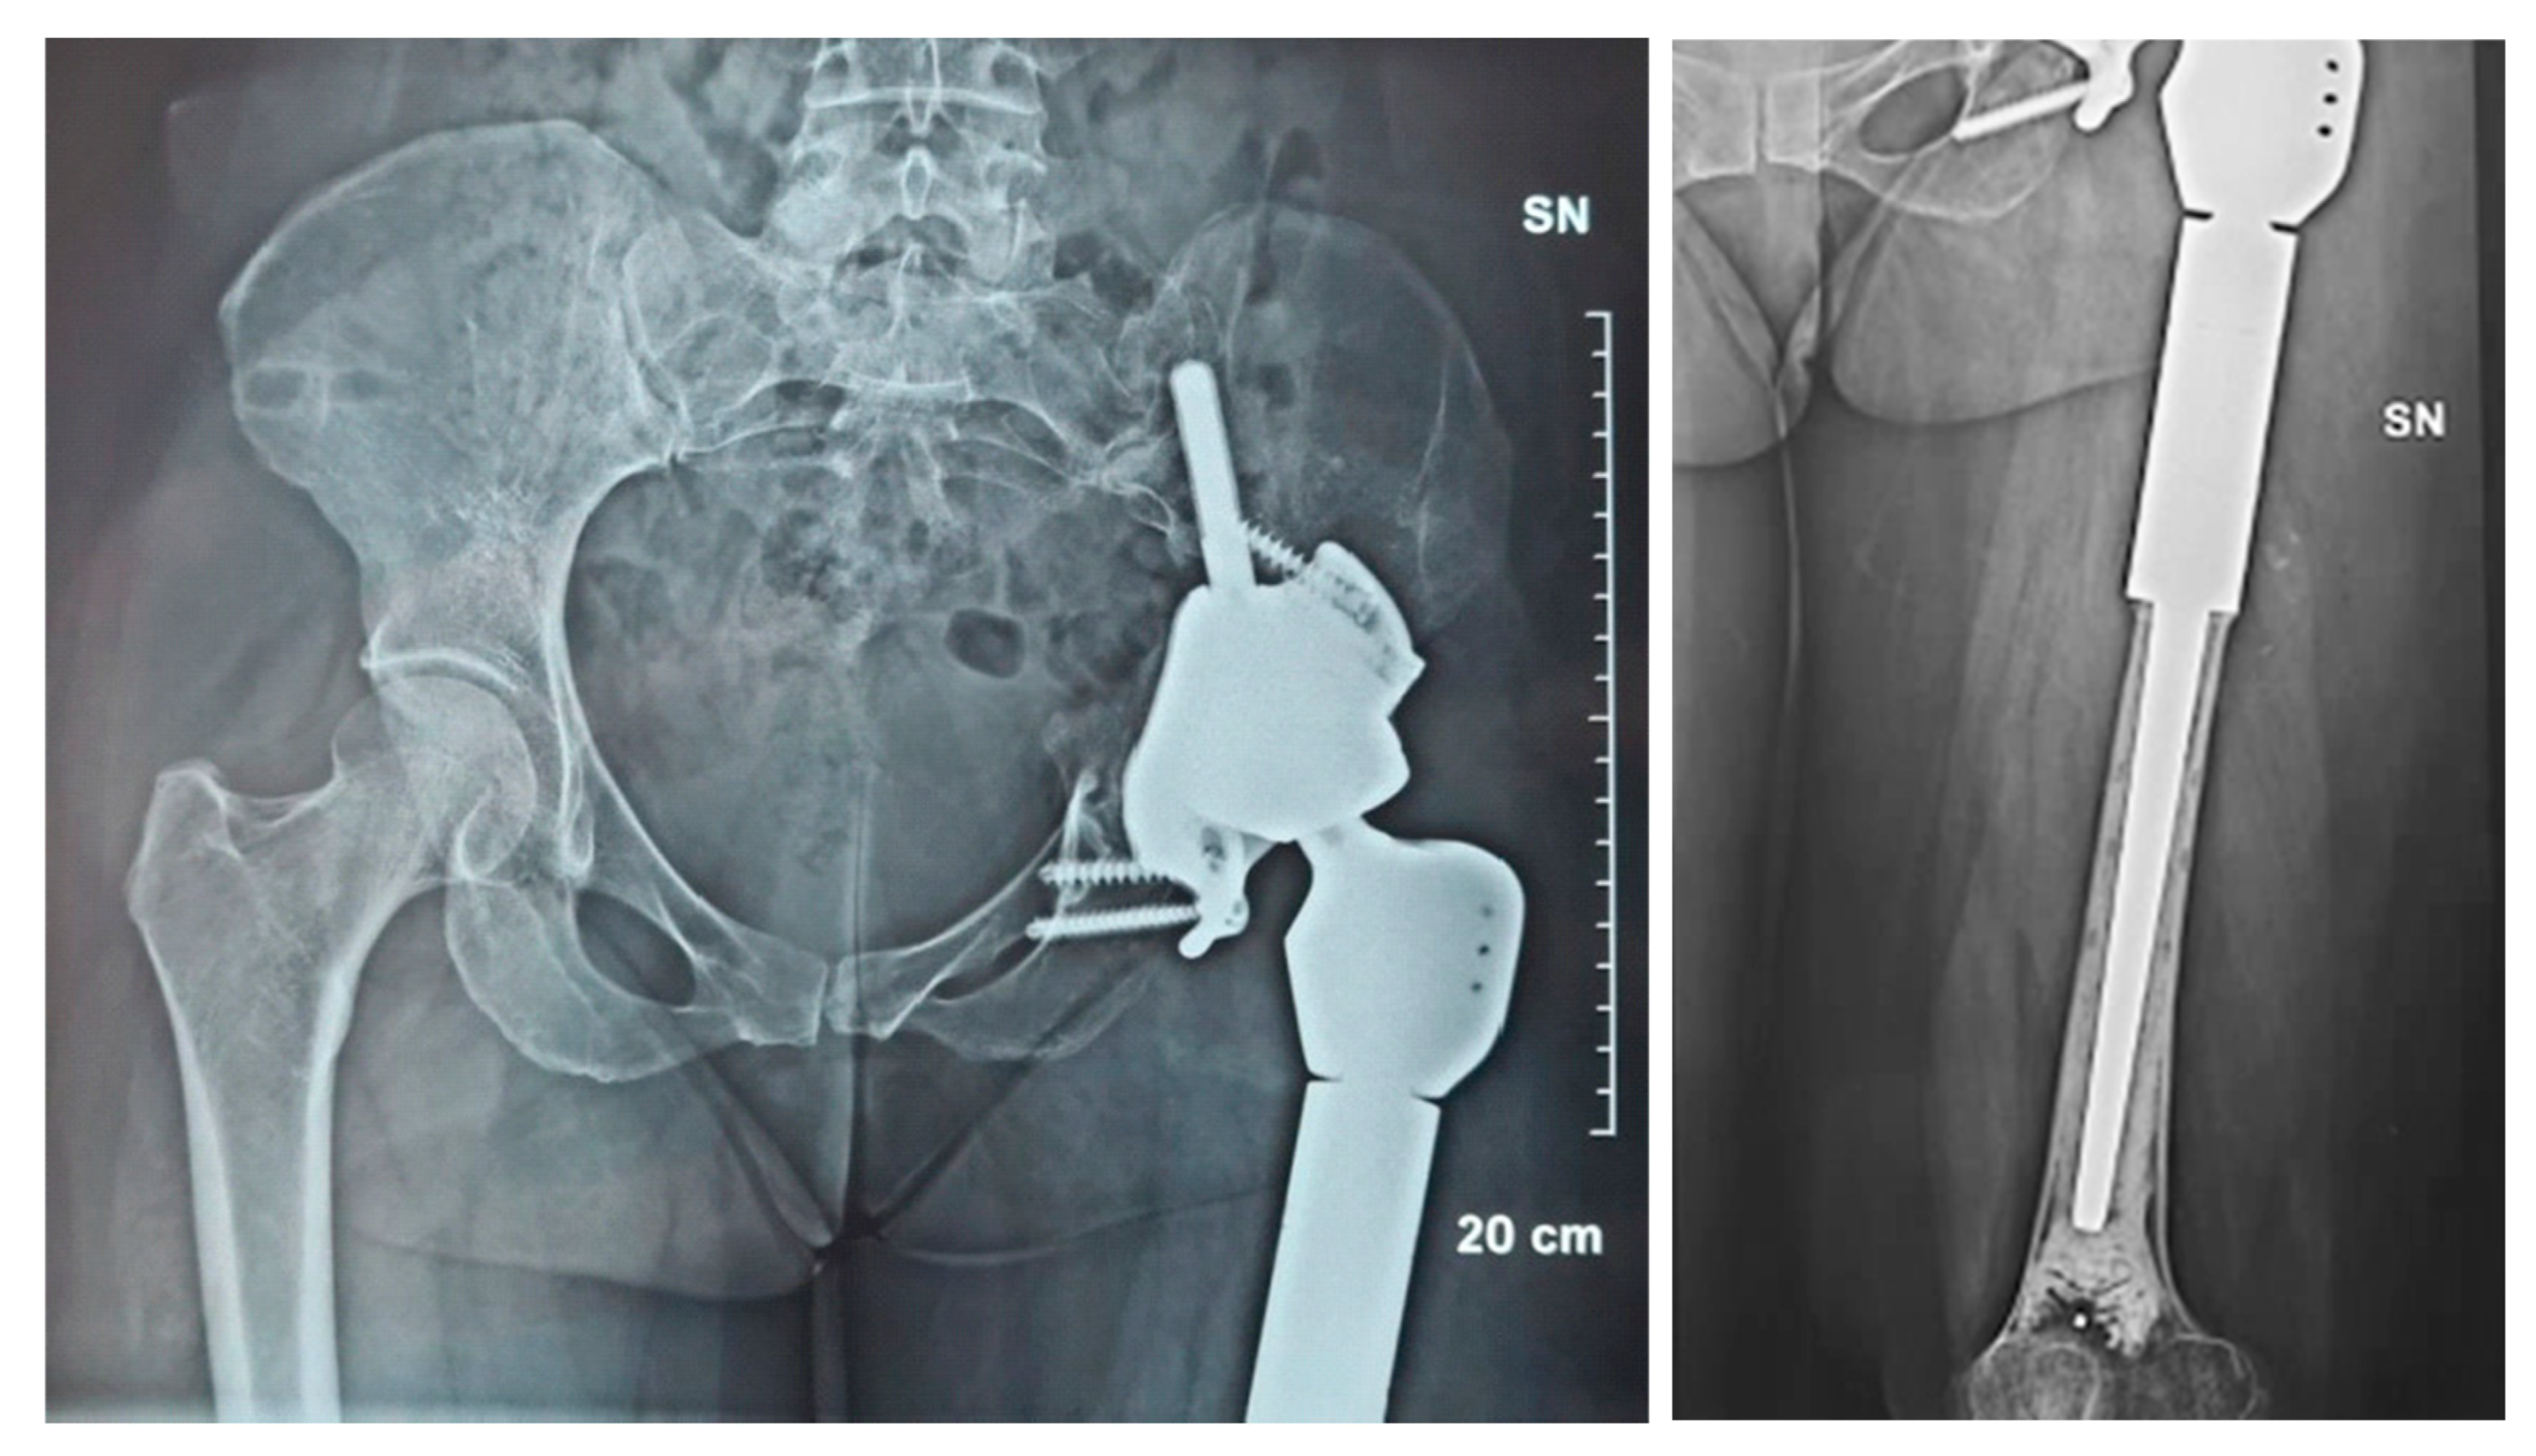

2.1. Case #1